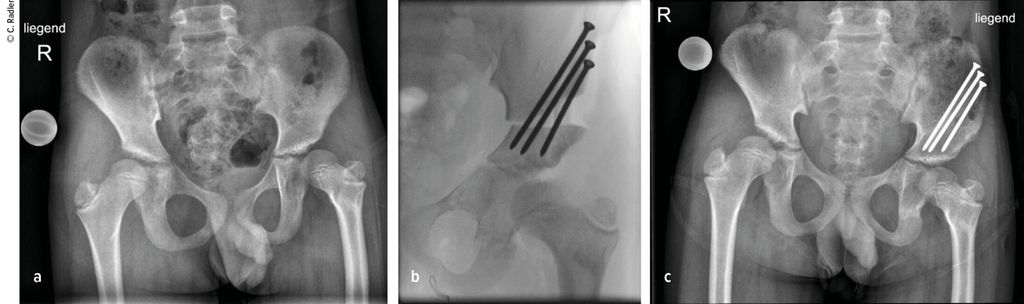

Der Typ 1B ist durch eine verzögerte Ossifikation/Pseudoarthrose subtrochantär oder im Schenkelhalsbereich charakterisiert, wobei auch ein kombinierter Typ mit Schenkelhals und subtrochantär verzögerter Ossifikation vorliegen kann. Klinisch imponiert neben der massiven Verkürzung die Außenrotations- und Beugekontraktur. In diesen Fällen ist eine komplexe Rekonstruktion, bestehend aus mehreren Schritten, erforderlich, die als Super-Hip-Operation subsumiert wird (Abb. 3).

Hierbei erfolgt der Zugang über einen breiten, lateralen Schnitt von der Mitte der Beckenschaufel über den Trochanterbereich oder auch den fallweise sichtbaren Haut-Dimple über die Mitte des Oberschenkels bis zum Knie bzw. bis zur Tuberositas tibiae, wenn eine gleichzeitige Stabilisierung des Kniegelenks erforderlich ist. Es wird die Faszie im Bereich des Intervalls zwischen Tensor fascia lata und Sartorius inzidiert und hier schließlich die proximale ventrale Grenze zum Absetzen der Faszien definiert. Distal erfolgt die Inzision etwas lateral der Patella. Diese beiden Inzisionen werden nun verbunden, dorsal wird die Faszie distal etwas posterior des intermuskulären Septums gespalten. Die Fascia lata kann entweder zur Stabilisierung des Kniegelenkes verwendet werden oder wird am Ende der Operation reseziert, um bei späteren Verlängerungen diese nicht zu behindern. Im nächsten Schritt erfolgt der Zugang über die Tensor-Lücke, wobei hier die Rectus-Sehne durchtrennt wird, was bereits einen Teil der Beugekontraktur korrigiert. Dies muss mit großer Vorsicht geschehen, da hier besonders bei schweren Formen des CFD der Femoralis-Nerv lateraler als üblich und damit näher am Rectus liegt. Im nächsten Schritt wird die Psoas-Sehne auf der Unterseite des Iliopsoas mit einer Klemme herausluxiert und ebenfalls durchtrennt. Ein weiterer wichtiger Faktor, besonders in Bezug auf die Abduktion und Außenrotation, ist der Piriformis, auch diese Sehne muss durchtrennt werden. Der Ischiadicus-Nerv ist hier sehr nahe und kann dabei oft gut identifiziert beziehungsweise in schweren Fällen auch neurolysiert werden.

Es wird dann auf die Beckenschaufel zugegangen und hier die Apophyse gesplittet und abgelöst. Dieser sogenannte Abductor-Slide entspannt weiter die kontrakte Muskulatur, da vor der Rückvernähung der Apophyse ein Teil des Beckenkamms abgetragen wird. Erst jetzt wird an das Femur herangegangen. Da besonders bei schweren Fällen an der Hüfte nur der Hüftkopfkern sichtbar ist, muss eine Arthrografie durchgeführt werden, um ein Setzen der Bohrdrähte für die Platte zu ermöglichen. Ein erster Bohrdraht wird vom palpierten Trochanter major in das Zentrum des Hüftkopfkernes gesetzt. Ein zweiter Bohrdraht wird etwa in 45° zu diesem wiederum in das Zentrum des Hüftkopfkerns gesetzt. Die Lage des Bohrdrahtes wird im Bildwandler überprüft und kann im seitlichen Strahlengang durch die Überlappung von Hüftkopfkern, Schenkelhals und Kapsel bestätigt werden. Dann kann die Platte schließlich über diesen eingebracht werden. Die Osteotomie des Femurs erfolgt dann in 90° zur liegenden Platte und wiederum in 90° zu diesem Schnitt. Medial muss auch das Periost durchtrennt und releast werden. Nun zeigt sich bereits, wie sehr das Femur verkürzt werden muss, um spannungsfreie Korrekturen zu ermöglichen. Die Platte wird jedoch erst nach der Acetabuloplastik fixiert, um Länge und Rotation korrekt einstellen zu können. Die Acetabuloplastik wurde klassisch als modifizierte Dega-Osteotomie durchgeführt, wobei sich über eine unikortikale Iliumosteotomie („Paley unicortical ilium osteotomy“) eine bessere Überdachung erreichen lässt.

Hierzu wird das Periost des Iliums bis zur Incisura ischiadica und bis knapp oberhalb des Acetabulums abgelöst. Medial wird das Periost im Bereich des Os pubis eingeschnitten, um eine bessere Mobilität des Fragmentes zu erzielen. Es wird dann von knapp oberhalb der Kapsel entlang der Incisura etwa 2–3cm nach proximal gemeißelt. Dann wird ein Bohrdraht gesetzt, der medial auf die Y-Fuge zielt. Entlang des Bohrdrahts wird die Osteotomie schließlich durchgeführt, wobei nur ganz ventral das Ileum medial durchtrennt wird, und hier in Richtung Pubis, wodurch wiederum kaum die mediale Kortikalis überschritten wird. Es kann nun die Osteotomieöffnung entsprechend aufgespreizt und ein Knochenstück aus der Femurverkürzung eingebracht werden. Entsprechend der Überlappung des distalen Femursegmentes in korrigierter Position werden schließlich auch die Resektionhöhe und das Ausmaß der Resektion des Femurs definiert. Nach entsprechender Verkürzung wird über Fixation der Platte schließlich auch die Rotation mit etwa 10° Antetorsion festgesetzt.

Typ 1B2 und 1B3

Bei den Typen 1B2 und 1B3, also bei Vorliegen einer verzögerten Ossifikation des Schenkelhalses, wird am Endenoch proximal der Klingenplatte BMP 2 über ein Bohrloch eingebracht. Nach Refixation der Rectussehne und Wundverschluss wird ein Becken-Bein-Gips für 4–6 Wochen angelegt. Während die Typen 1B mit entsprechender Erfahrung gut und reproduzierbar rekonstruiert werden können. ist dies beim Typ 2 deutlich schwieriger und mit deutlich mehr Risiko eines Versagens des Verfahrens und entsprechenden Komplikationen verbunden.

Typ 2A

Beim Typ 2A liegt zusätzlich eine fibröse Pseudarthrose zwischen Hüftkopf und Femurschaft vor, wobei die Apophyse des Femurs vorhanden ist. Für die Rekonstruktion muss die Hüftkapsel eröffnet werden und die Anlage des Schenkelhalses im Bereich der Pseudarthrose angefrischt und gegenübergestellt und schließlich mit Cerclagen unter Kompression gesetzt werden. Erst dann können die anderen Schritte der Super-Hip-Operation durchgeführt werden. Weiters ist zum Schutz der instabilen Hüfte ein temporärer Fixateur hüftübergreifend erforderlich.